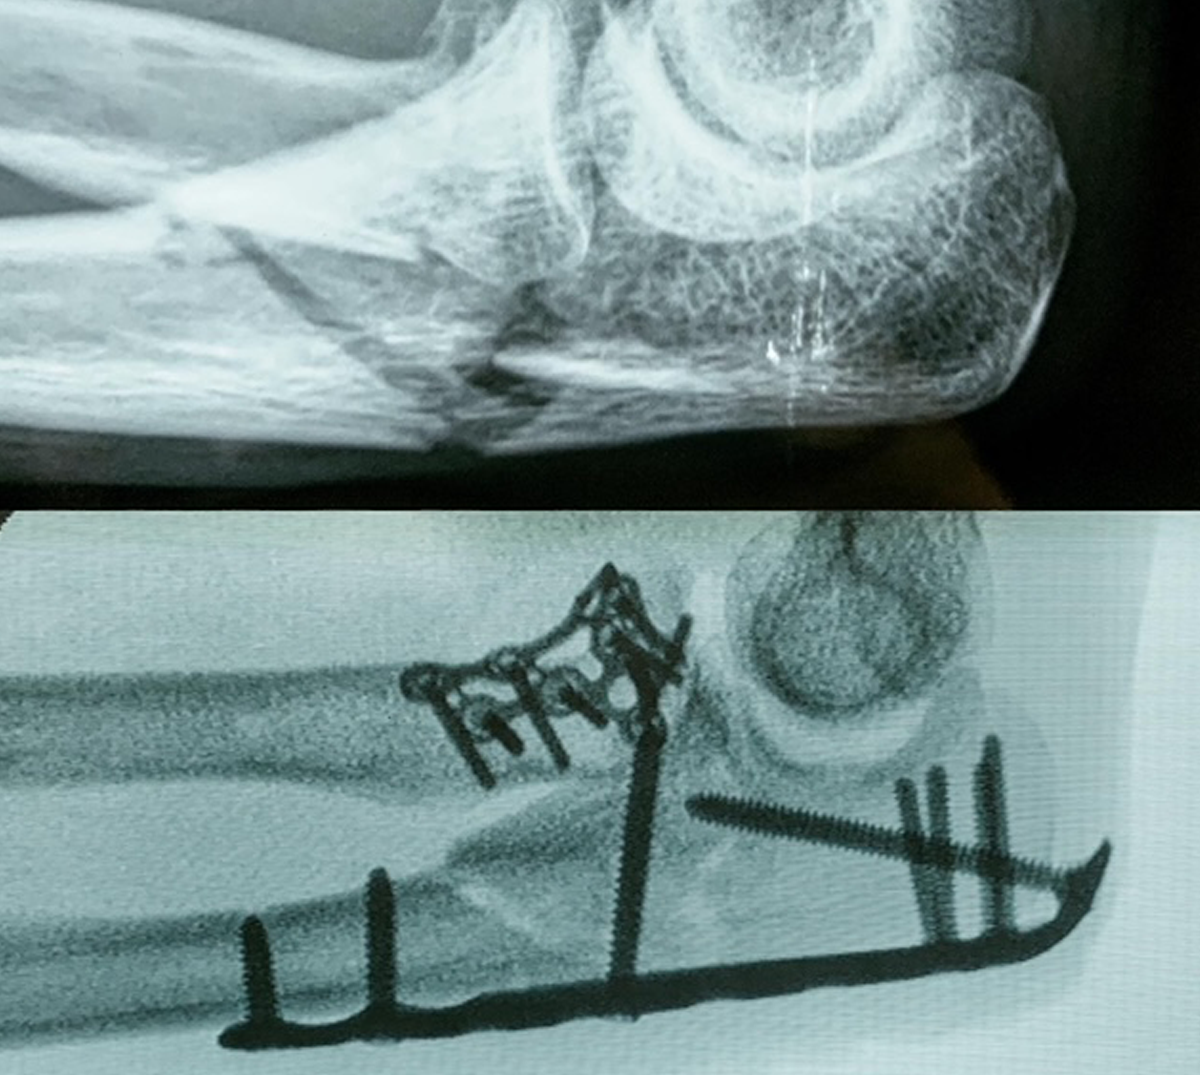

TRATAMIENTO DE FRACTURAS

Las fracturas o el común llamado “hueso roto” deben ser tratadas con inmovilización por medio de férulas y en casos más graves, con manejo quirúrgico.

La recuperación de una fractura tiene que llevarse siempre junto a un ortopedista. Esto para reducir complicaciones y proporcionar las mejores condiciones para que el hueso sane adecuadamente.